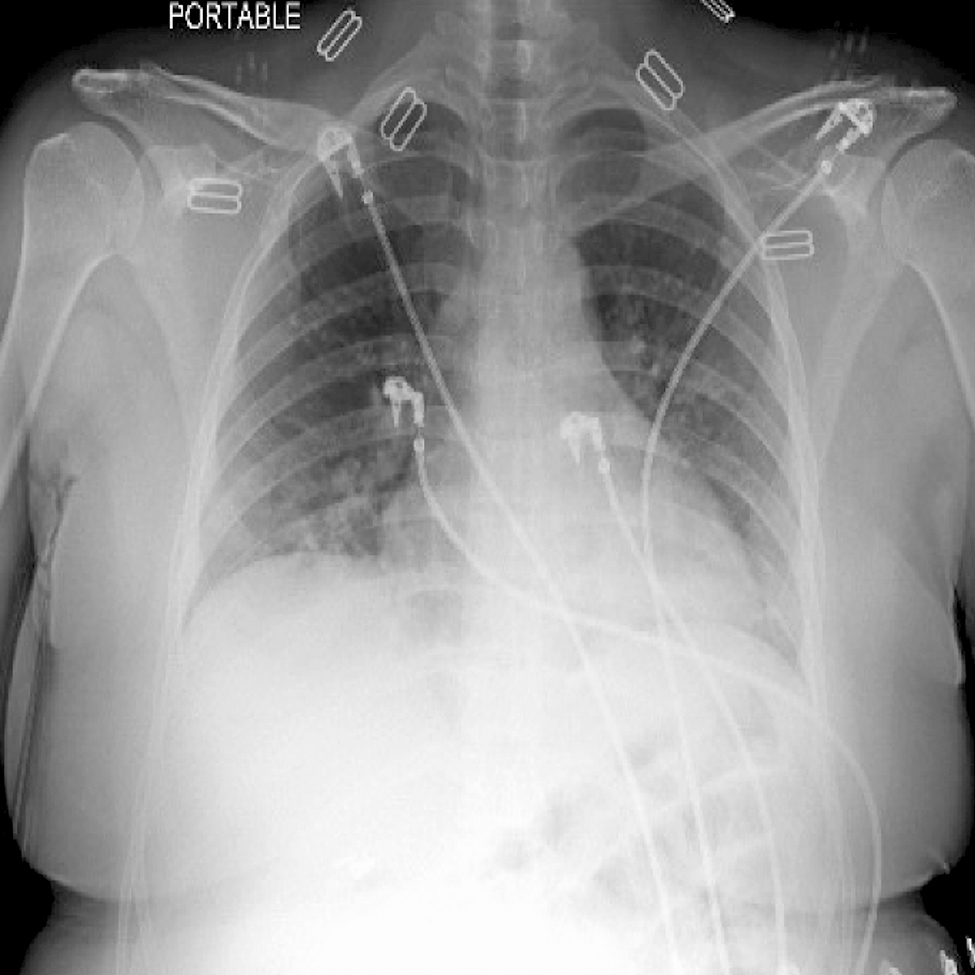

She returned to the hospital that same night with gradually worsening shortness of breath, myalgias, low grade fever and worsening headache. On presentation she was tachycardia (heart rate 110 bpm), tachypneic (respiratory rate 24), hypotensive (blood pressure 80 s/50 s), and she had an oxygen saturation of 95% on room air. Labs for her second admission are summarize in Table 2. Chest X-ray at that time suggested possible pneumonia (Figure 2). The patient was admitted to the general medicine service where she received ceftriaxone for one day, azithromycin for a total of seven days and supplemental oxygen with a maximum oxygen requirement of 3 L nasal cannula. She was discharged on hospital day 6 once weaned from oxygen. She continues to do well. Written informed consent was obtained from the patient for publication.

Chest X-ray on representation for second admission. Radiologic impression: patchy airspace opacification in the lower lobes with vascular crowding.